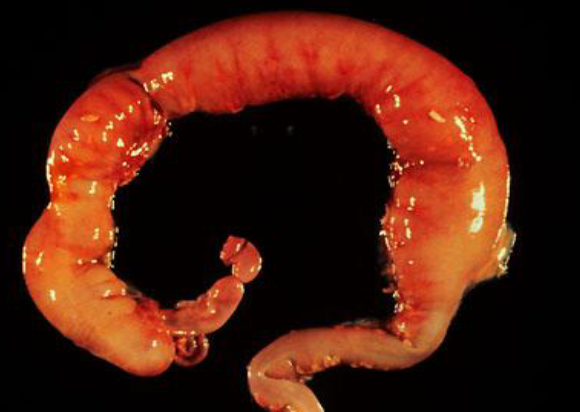

necrotizing enterocolitis (NEC) totalis

inflammation/infection of bowel causing tissue death, perforation, sepsis; commonly affects premature infants.

hirschsprung’s disease

migration of ganglion cells is incomplete; colon movement is improperly regulated causing stool obstructions